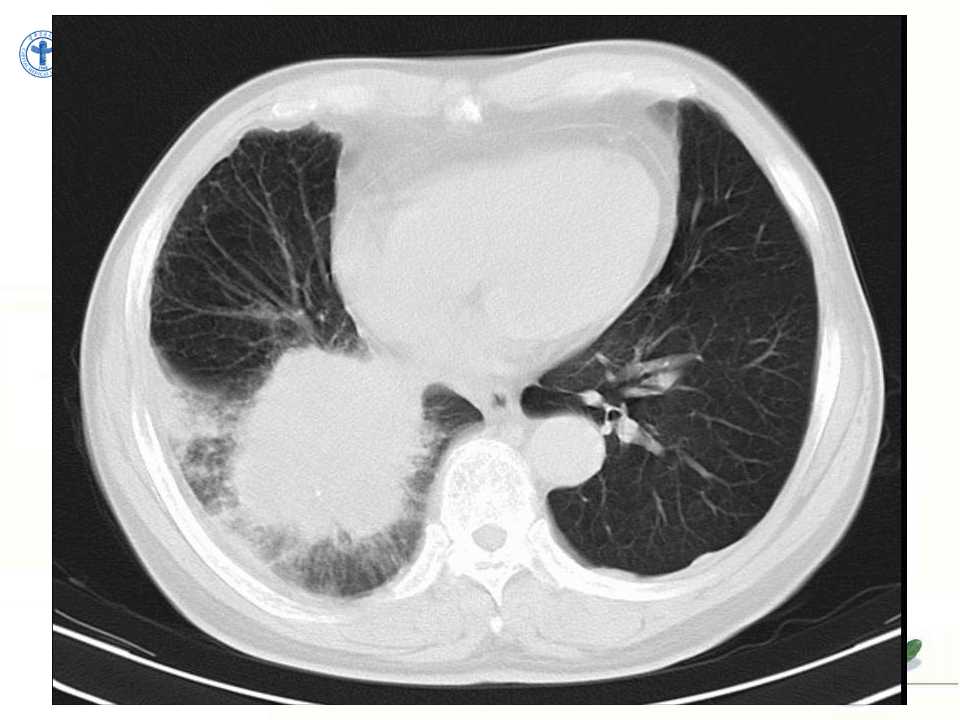

肺癌的影像学检查